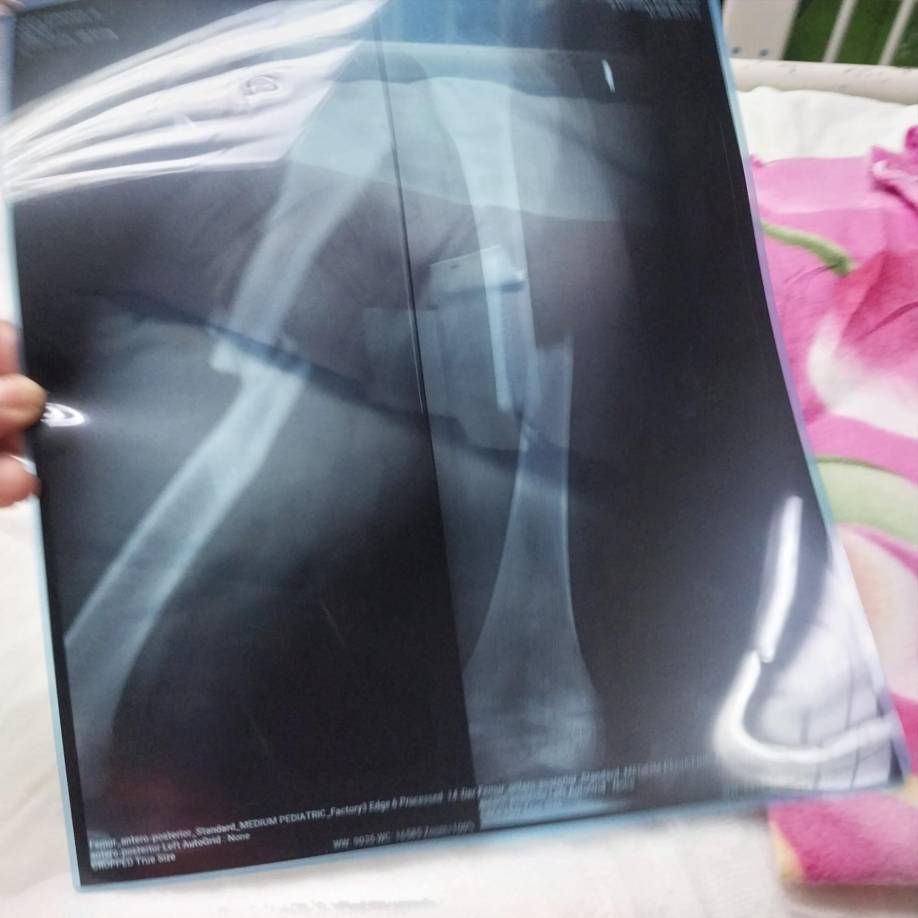

11 / 13Fernanda tiene sus dos piernas quebradas. Acá la radiografía de la menor.